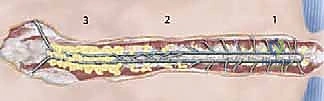

Once the rod is approximated to the spine, the sublaminar wires are sequentially tightened around the rod.

Tightening begins at the apex of the curve to draw the spine to the rod, and then proceeds proximally and distally. The wires must be tensioned symmetrically to avoid asymmetric pull-out.

The wire ends are cut short and meticulously bent over the rod to prevent soft tissue irritation.

A robust arthrodesis is the ultimate goal; the hardware is merely an internal splint until biological fusion occurs. The remaining exposed posterior elements (laminae, transverse processes) are aggressively decorticated using a high-speed burr or gouges until bleeding cancellous bone is exposed.

Copious amounts of bone graft—typically a mixture of local autograft harvested from the spinous processes and facet joints, combined with massive volumes of allograft (cancellous chips and demineralized bone matrix)—are packed meticulously into the decorticated gutters.